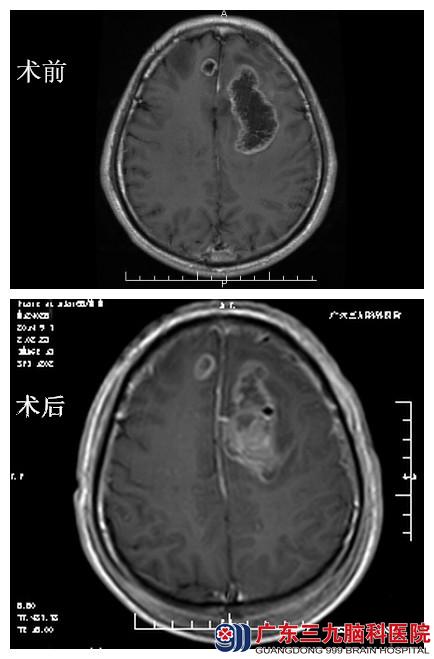

广东三九脑科医院进一步行头颅检查,MRI平扫+增强检查提示:1、双侧额叶及胼胝区占位性病变,考虑高级别胶质瘤,以胶质母细胞瘤可能性大。2、脑白质多发脱髓鞘灶。MRS检查提示:左侧额叶病变感兴趣区Cho峰升高,NAA峰明显下降,可见Lip峰,支持偏恶性肿瘤诊断。3D-ASL检查提示:侧额叶及胼胝体区多发病变呈低灌注。

检查无明显手术禁忌症,于2014年9月4日,神经外三科为其在全麻下“左侧额顶叶占位切除术”。手术顺利,术后15日行头部适形放疗。经治疗,黄伯言语不清较前好转,肢体活动基本正常,遂出院。病理报告:胶质母细胞瘤 WHO 4级。